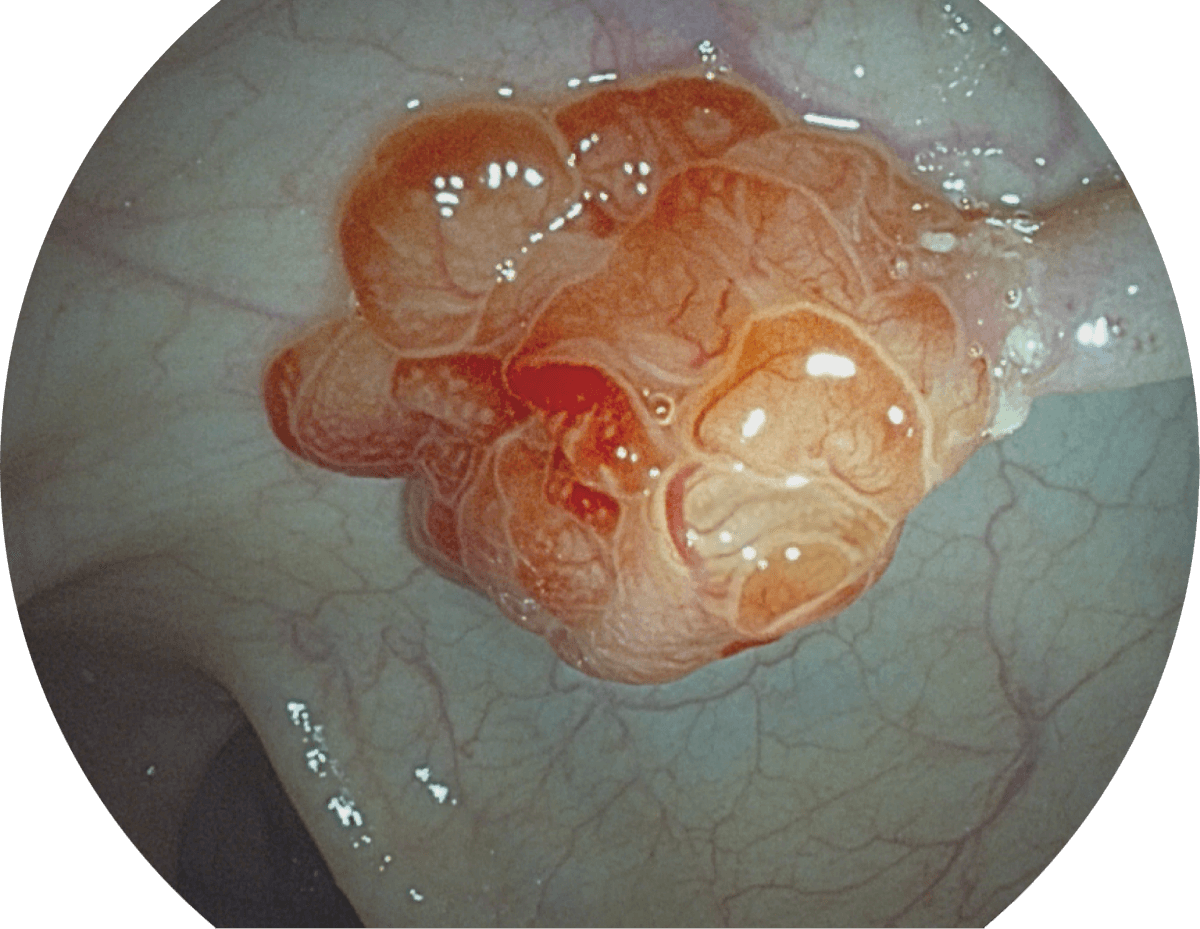

具有聚谱成像技术(SFI)及光电复合染色成像技术(VIST),可完美呈现粘膜细节及病变特征。

(Spectral Focused lmaging, SFI)

( Versatile Intelligent Staining Technology, VIST )

WL

SFI

VIST